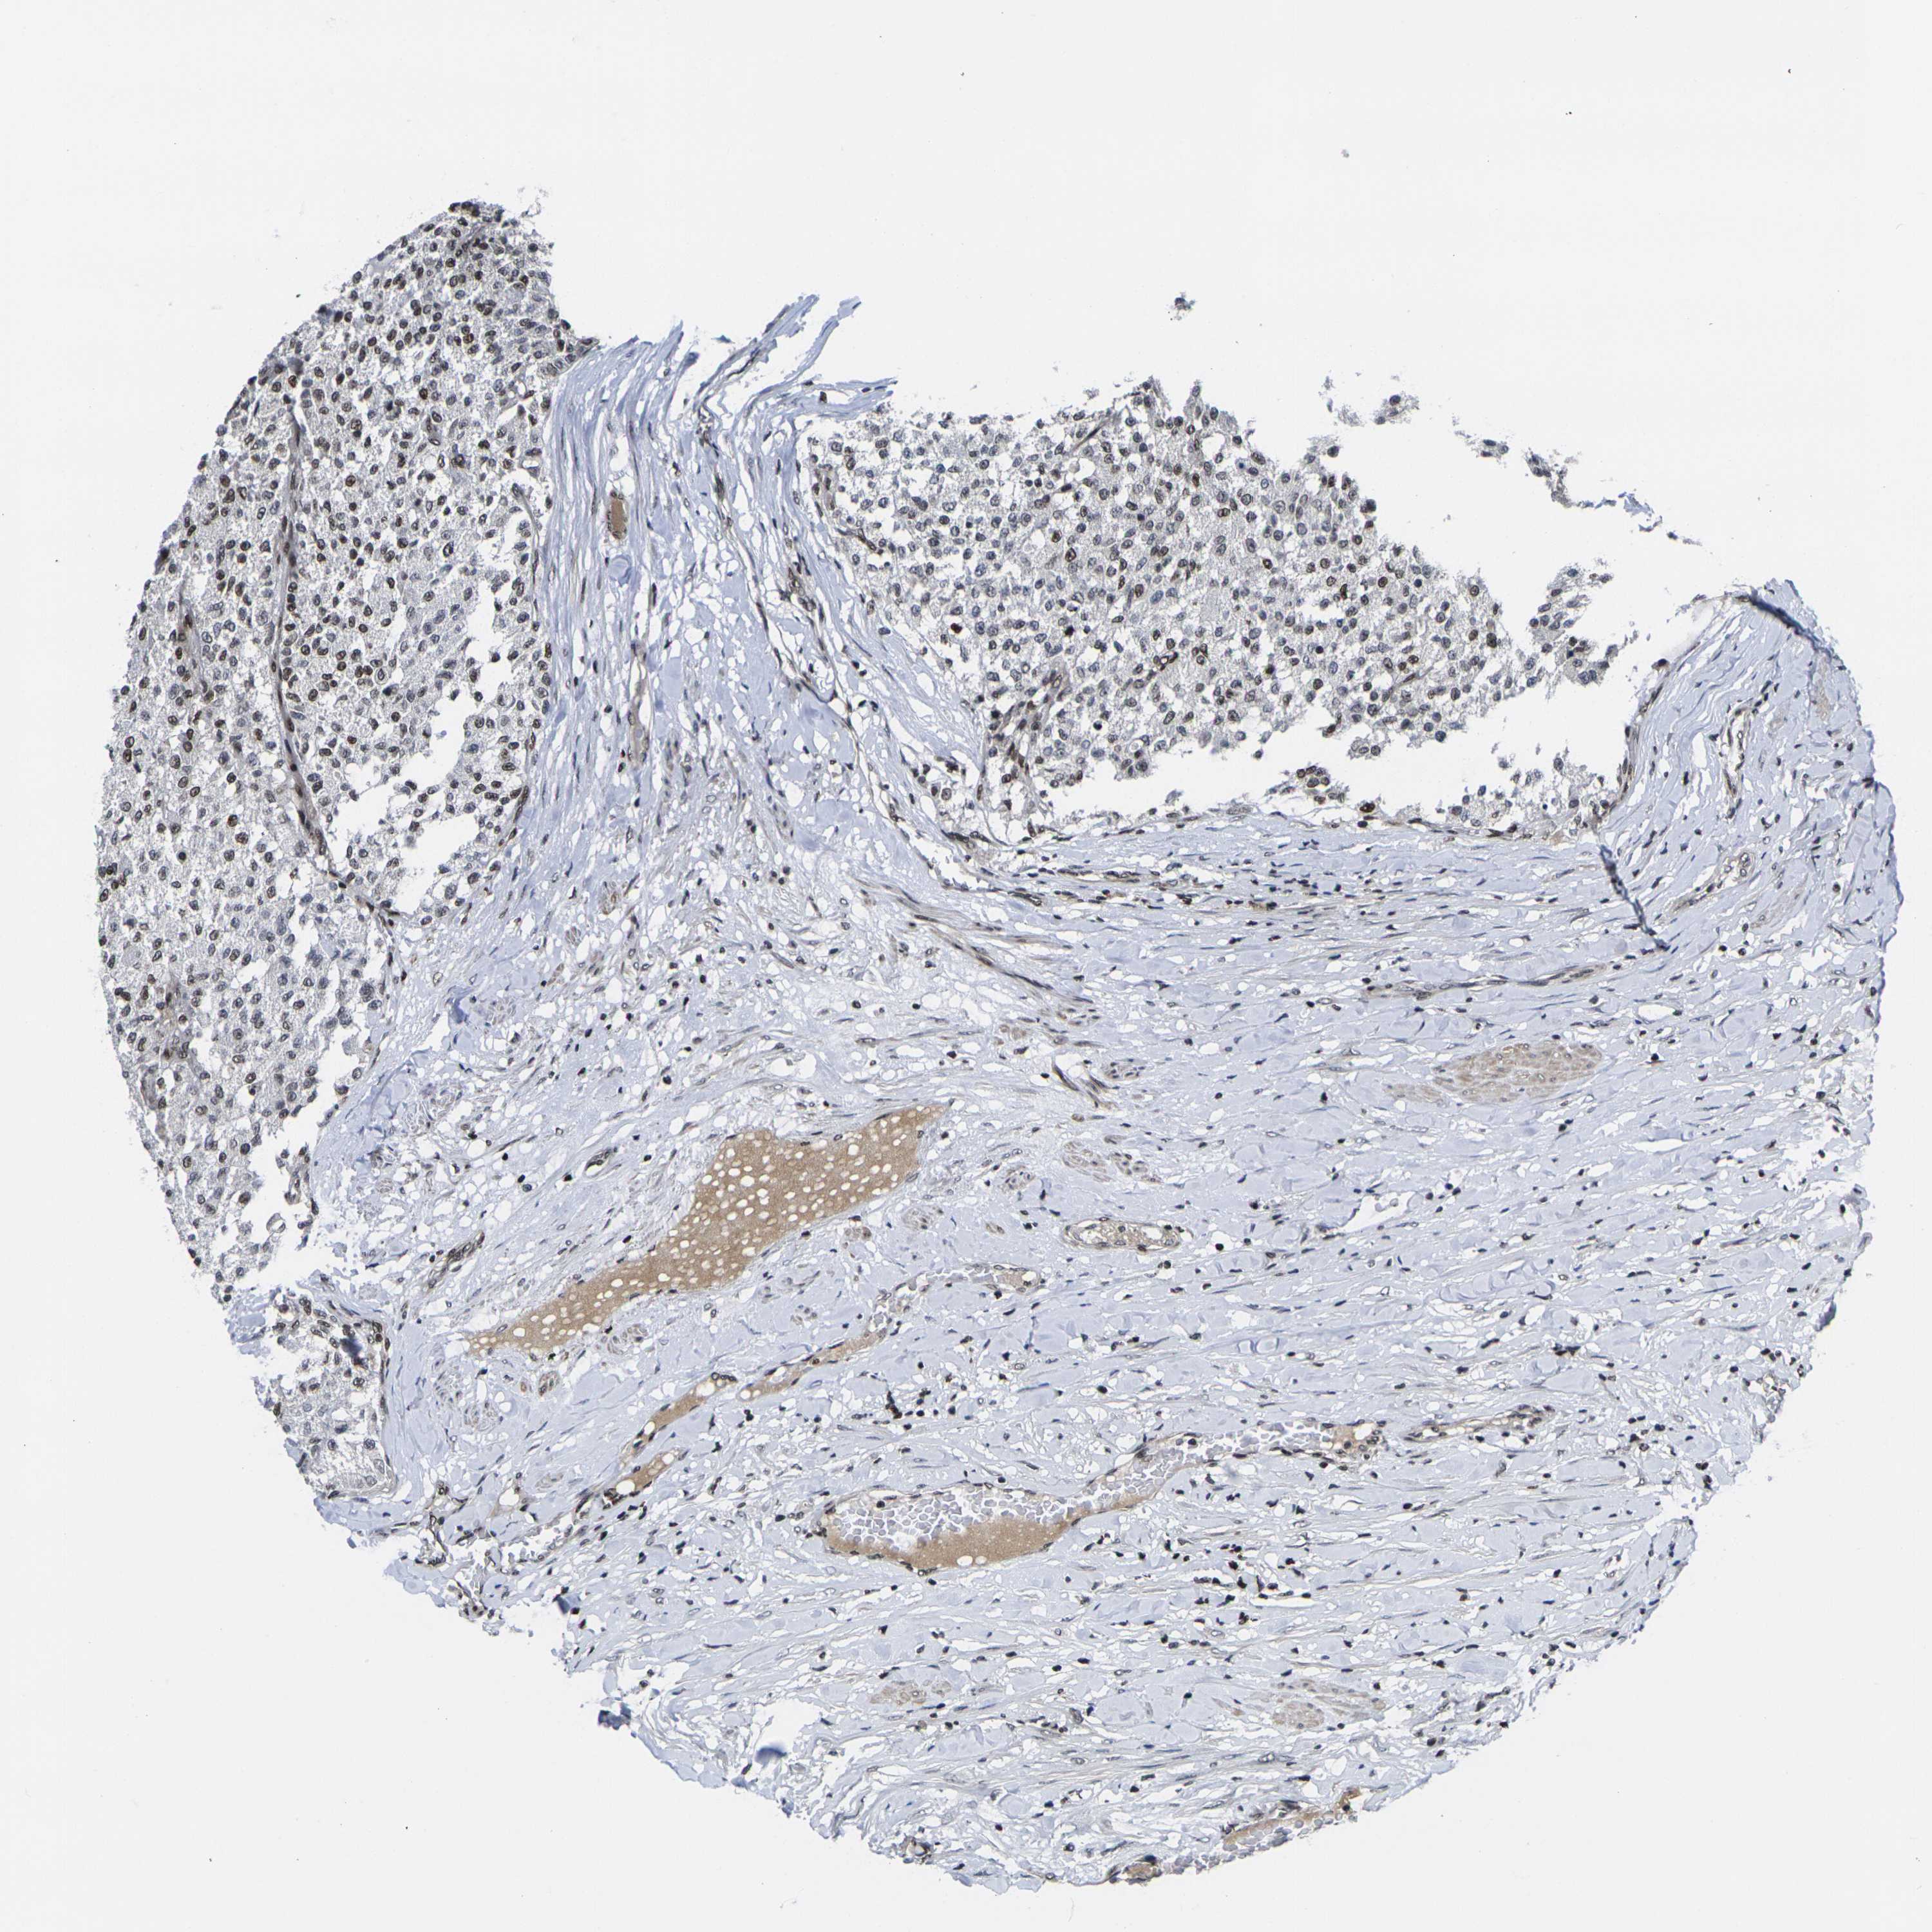

TESTIS CANCER - Protein expressioni

A mouse-over function shows sample information and annotation data. Click on an image to view it in a full screen mode. Samples can be filtered based on level of antibody staining by selecting one or several of the following categories: high, medium, low and not detected. The assay and annotation is described here.

Note that samples used for immunohistochemistry by the Human Protein Atlas do not correspond to samples in the TCGA dataset.

Antibody stainingi

Antibody staining in the annotated cell types in the current human tissue is reported as not detected, low, medium, or high, based on conventional immunohistochemistry profiling in selected tissues. This score is based on the combination of the staining intensity and fraction of stained cells.

Each image is clickable and will lead to virtual microscopy that enables deeper exploration of all samples and also displays staining intensity scores, fraction scores and subcellular localization as well as patient and tissue information for each sample.

Antibody HPA068431

Antibody CAB012235

Seminoma, NOS

Carcinoma, Embryonal, NOS